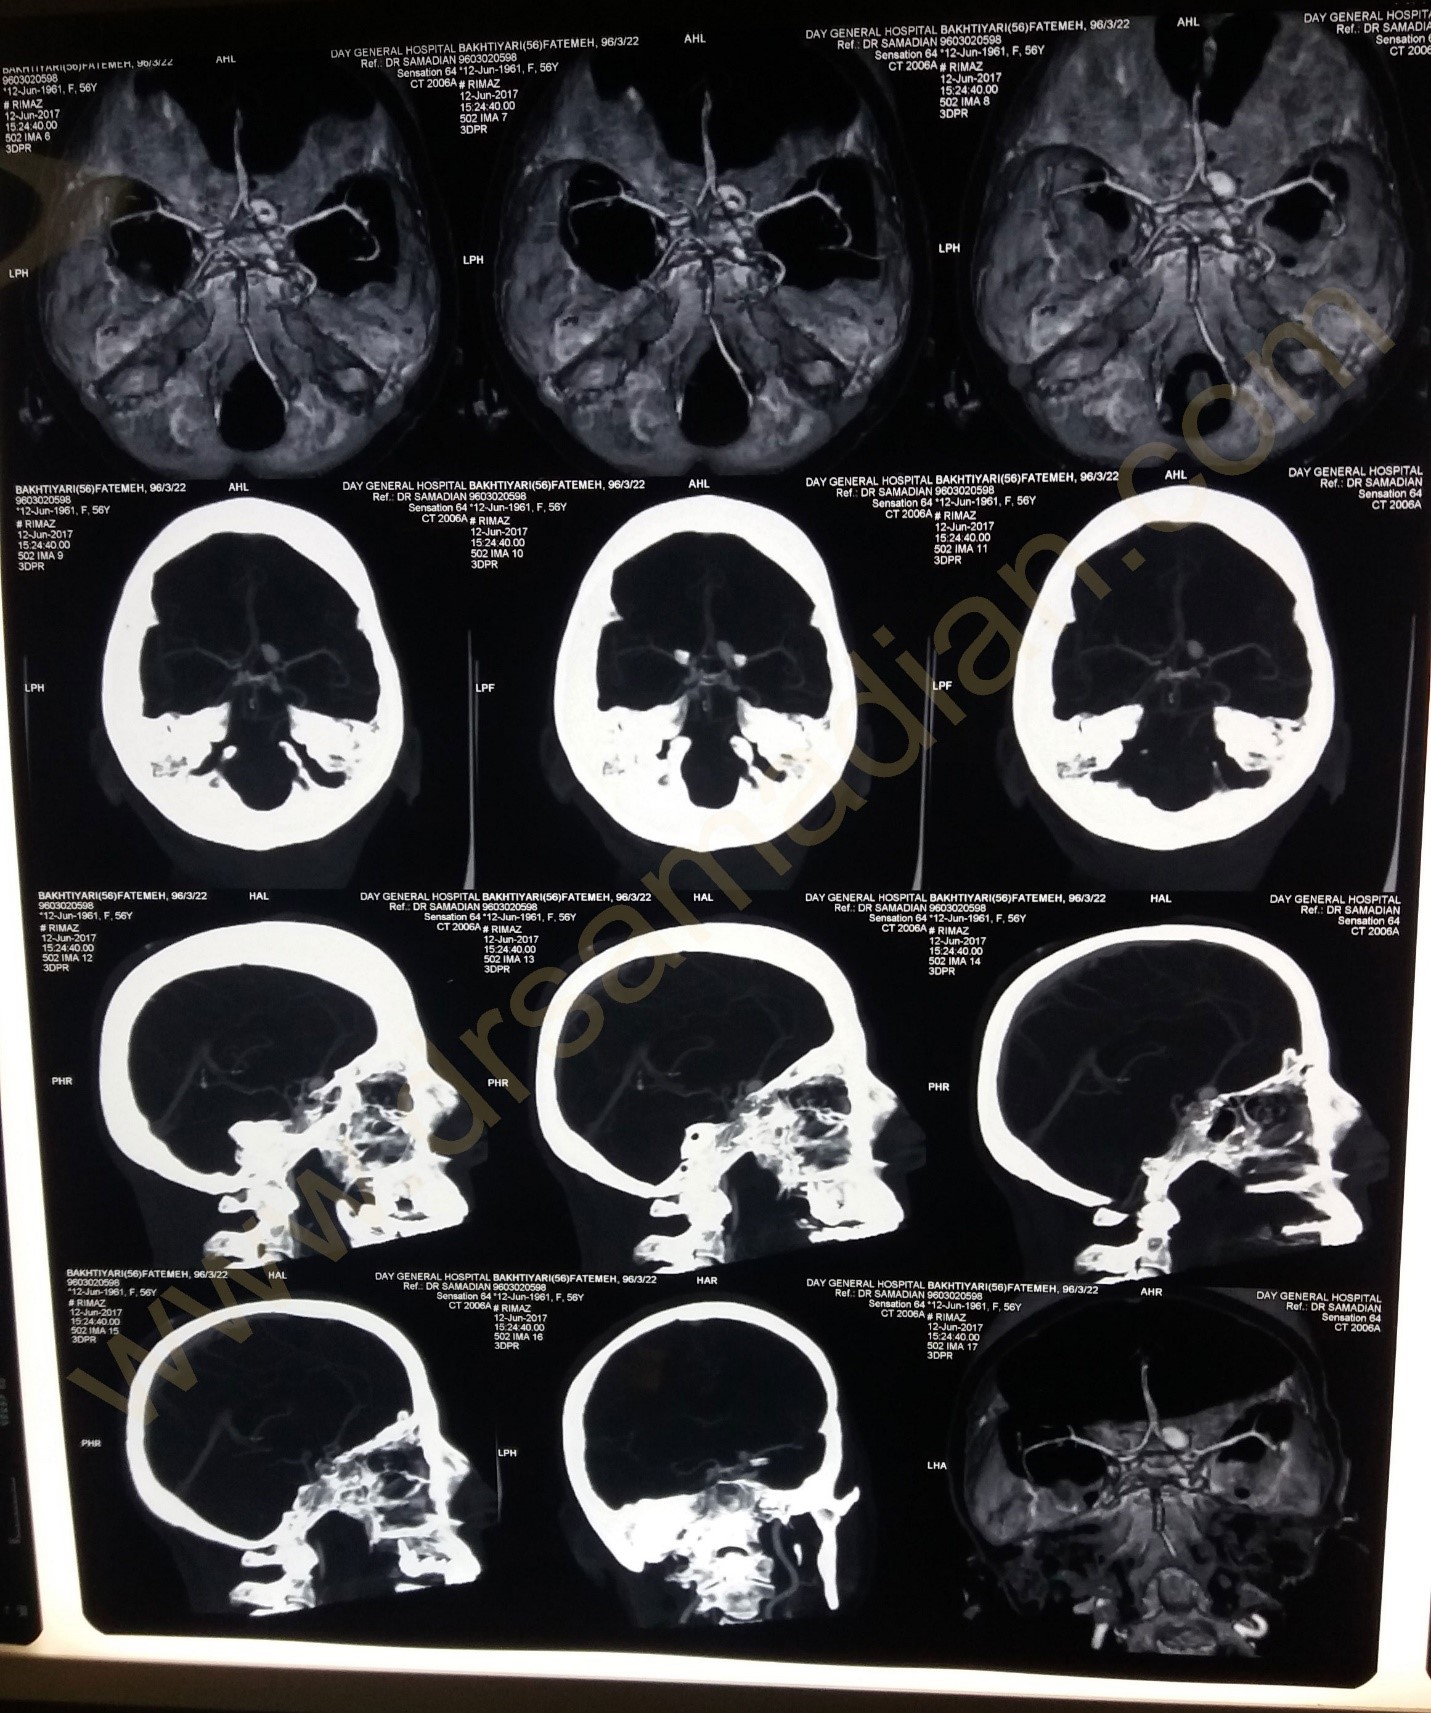

تصاویر یک بیمار آنوریسم مغزی را در زیر مشاهده میکنید :

بیمار خانم ۵۶ ساله که از بیماران قدیمی بوده که به علت دیسک کمر چند سال قبل عمل شده بودند به علت کاهش بینایی چشم راست مراجعه کرده در بررسیها تشخیص آنوریسم بزرگ شریان کاروتید راست داشتند و نیز پس از بررسیهای کامل تحت عمل جراحی کلیپ آنوریسم به صورت میکروسکوپی قرار گرفتند بینایی بیمار بهتر شد و عارضه خاصی نداشت.